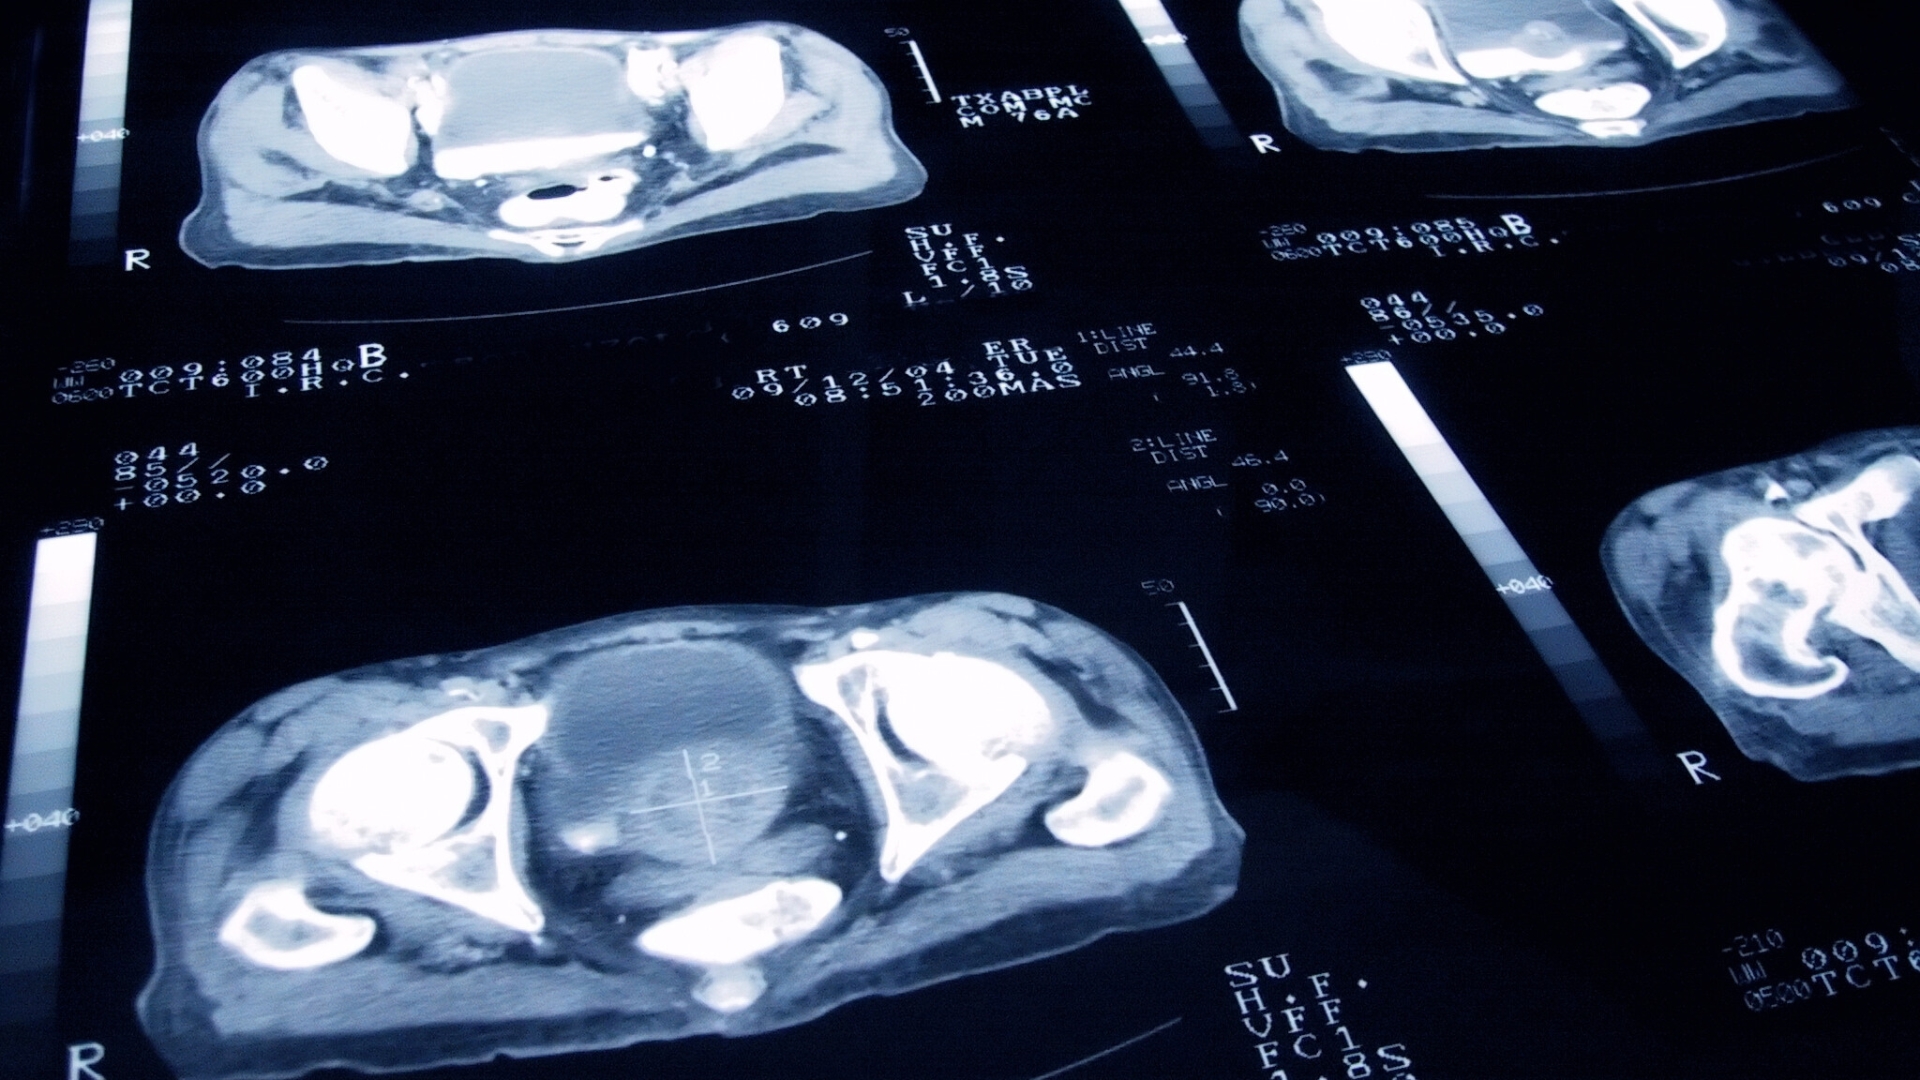

سرطان البروستاتا هو نوع من السرطان الذي ينمو في غدة البروستاتا، وهي غدة صغيرة لدى الرجال تنتج جزءًا من السائل المنوي. يعتبر من أكثر أنواع السرطان شيوعًا بين الرجال، حيث تختلف حدته من حالات بطيئة النمو قد لا تحتاج إلى علاج، إلى حالات عدوانية قد تنتشر بسرعة. للكشف المبكر دور مهم في إدارة سرطان البروستاتا والحد من مضاعفاته. في هذا المقال، نستعرض أسباب سرطان البروستاتا، الأعراض، وطرق الوقاية والعلاج.